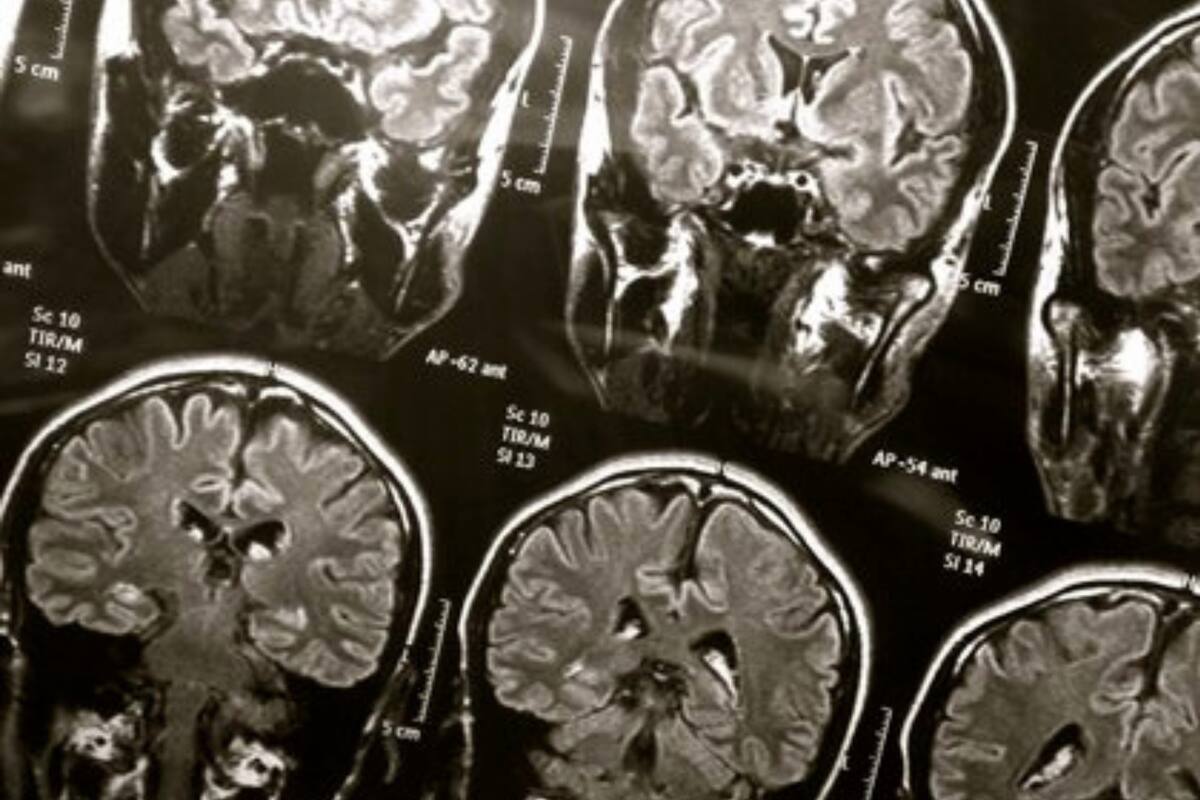

Las emociones inducidas por la música se pueden predecir a partir de escáneres cerebrales, según observaron investigadores de la Universidad de Turku (Finlandia) tras analizar a 102 personas.

Los especialistas utilizaron un algoritmo de aprendizaje automático para mapear qué regiones del cerebro se activan cuando las diferentes emociones inducidas por la música se separan unas de otras. "Basándonos en la activación de la corteza auditiva y motora, pudimos predecir con precisión si el sujeto de la investigación estaba escuchando música alegre o triste. La corteza auditiva procesa los elementos acústicos de la música, como el ritmo y la melodía", explicaron.

Por lo tanto, la activación de la corteza motora puede estar relacionada con el hecho de que la música inspira sentimientos de movimiento en los oyentes incluso cuando están escuchando música mientras se mantienen quietos en una máquina de resonancia magnética.

Los investigadores también descubrieron qué regiones del cerebro se activan cuando los participantes de la investigación vieron videos que evocan emociones fuertes y probaron si las mismas regiones se activaron cuando los participantes estaban escuchando música que evoca emociones.

Los resultados sugirieron que las emociones evocadas por las películas y la música se basan parcialmente en el funcionamiento de diferentes mecanismos en el cerebro. "Las películas, por ejemplo, activan las partes más profundas del cerebro que regulan las emociones en situaciones de la vida real. Escuchar música no activó fuertemente estas regiones ni su activación separó las emociones inducidas por la música entre sí", detallaron los expertos.

Esto puede deberse al hecho de que las películas pueden copiar de manera más realista los eventos de la vida real que evocan emociones y, por lo tanto, activan los mecanismos emocionales innatos. En cuanto a las emociones inducidas por la música, se basan en las características acústicas de la música y están coloreadas por influencias culturales e historia personal.